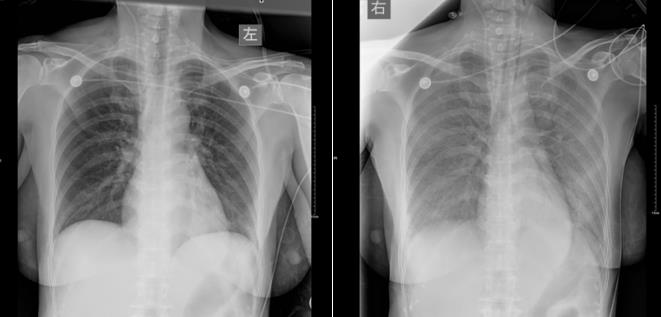

经过以上处理后,患者病情无好转,持续恶化,第二日患者肺部开始出现肺水肿,气喘明显,呼吸衰竭,立即需要行机械通气治疗。(下图所见其肺部情况)

同时患者开始少尿,皮肤巩膜黄染,肾功能、肝功能急剧损害,电解质紊乱,代谢性酸中毒,血乳酸持续升高。患者经过抢救治疗后,第三日还是宣布死亡了。病情的进展是有多么的迅猛,看以下这些指标的变化就能明了了。